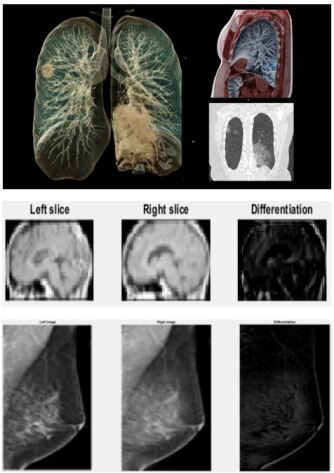

A paradigm of HP towards COVID-19 is represented by Image Frame Algebra (IFA) [15, 18], which processes and diagnoses suspectedly infected lung images by efficient and accurate hypersignal handling according to a set of IFA operators. In IFA, a generic image model is an SM based on Eq. (12). According to IFA, the differential algorithm for COVID-19 images manipulations is implemented as follows:

The operations of image differentiation in IFA may be expressed according to Eq. (II-B) as follows:

{Space Differentiation:Diffs=δs(IL,IR)Time Differentiation:Difft=δt(It1,It1)casesSpace Differentiation:superscript𝐷𝑖𝑓subscript𝑓𝑠subscript𝛿𝑠subscript𝐼𝐿subscript𝐼𝑅Time Differentiation:superscript𝐷𝑖𝑓subscript𝑓𝑡subscript𝛿𝑡subscript𝐼subscript𝑡1subscript𝐼subscript𝑡1\displaystyle\left\{\begin{array}[]{ll}\text{Space Differentiation:}&Dif\!f_{s}\buildrel\wedge\over{=}\delta_{s}(I_{L},I_{R})\\ \text{Time Differentiation:}&Dif\!f_{t}\buildrel\wedge\over{=}\delta_{t}(I_{t_{1}},I_{t_{1}})\end{array}\right. (17)

where the first model expresses a differentiation between the left and right images of a symmetric structure such as lungs, breasts, and the brain. The second model denotes a sequential differentiation of image series with respect to time.

For instances, the results of COVID-19 affected lung images, brain tumors, and breast tumors may be diagnosed according to the generic image differential algorithm (Eqs. (II-B) and (17)), respectively, as shown in Fig. 2.

Refer to caption

Figure 2: Formal diagnoses of COVID-19 affected lung images and other applications by image differentiations.